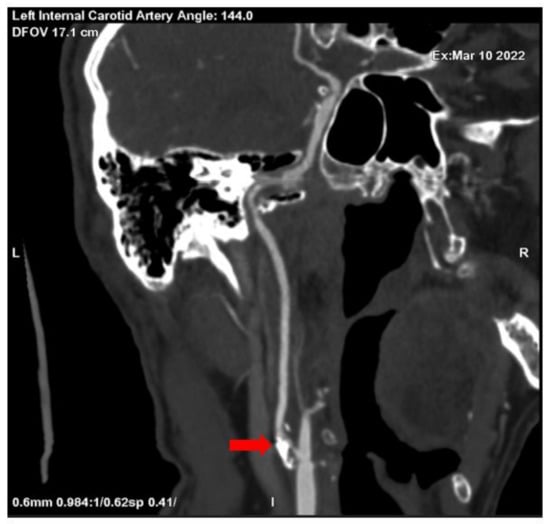

Brain magnetic resonance imaging (MRI) with magnetic resonance angiography (MRA) with intravenous contrast was performed with sequences as follows: FLAIR, MP reconstructions, T2 SE ax, DW ax, SW ax, MRA, 3D TOF, and MIP reconstructions, T2 core with fat saturation, T1 SE sag post-contrast. The radiological findings included diffusely expanded ventricles and cortical grooves, as well as segmentary stenosis in the extracranial part of the left internal carotid artery (see Figure 3).

Figure 3. Segmentary stenosis in the extracranial part of the left internal carotid artery (MRA) (red arrays).